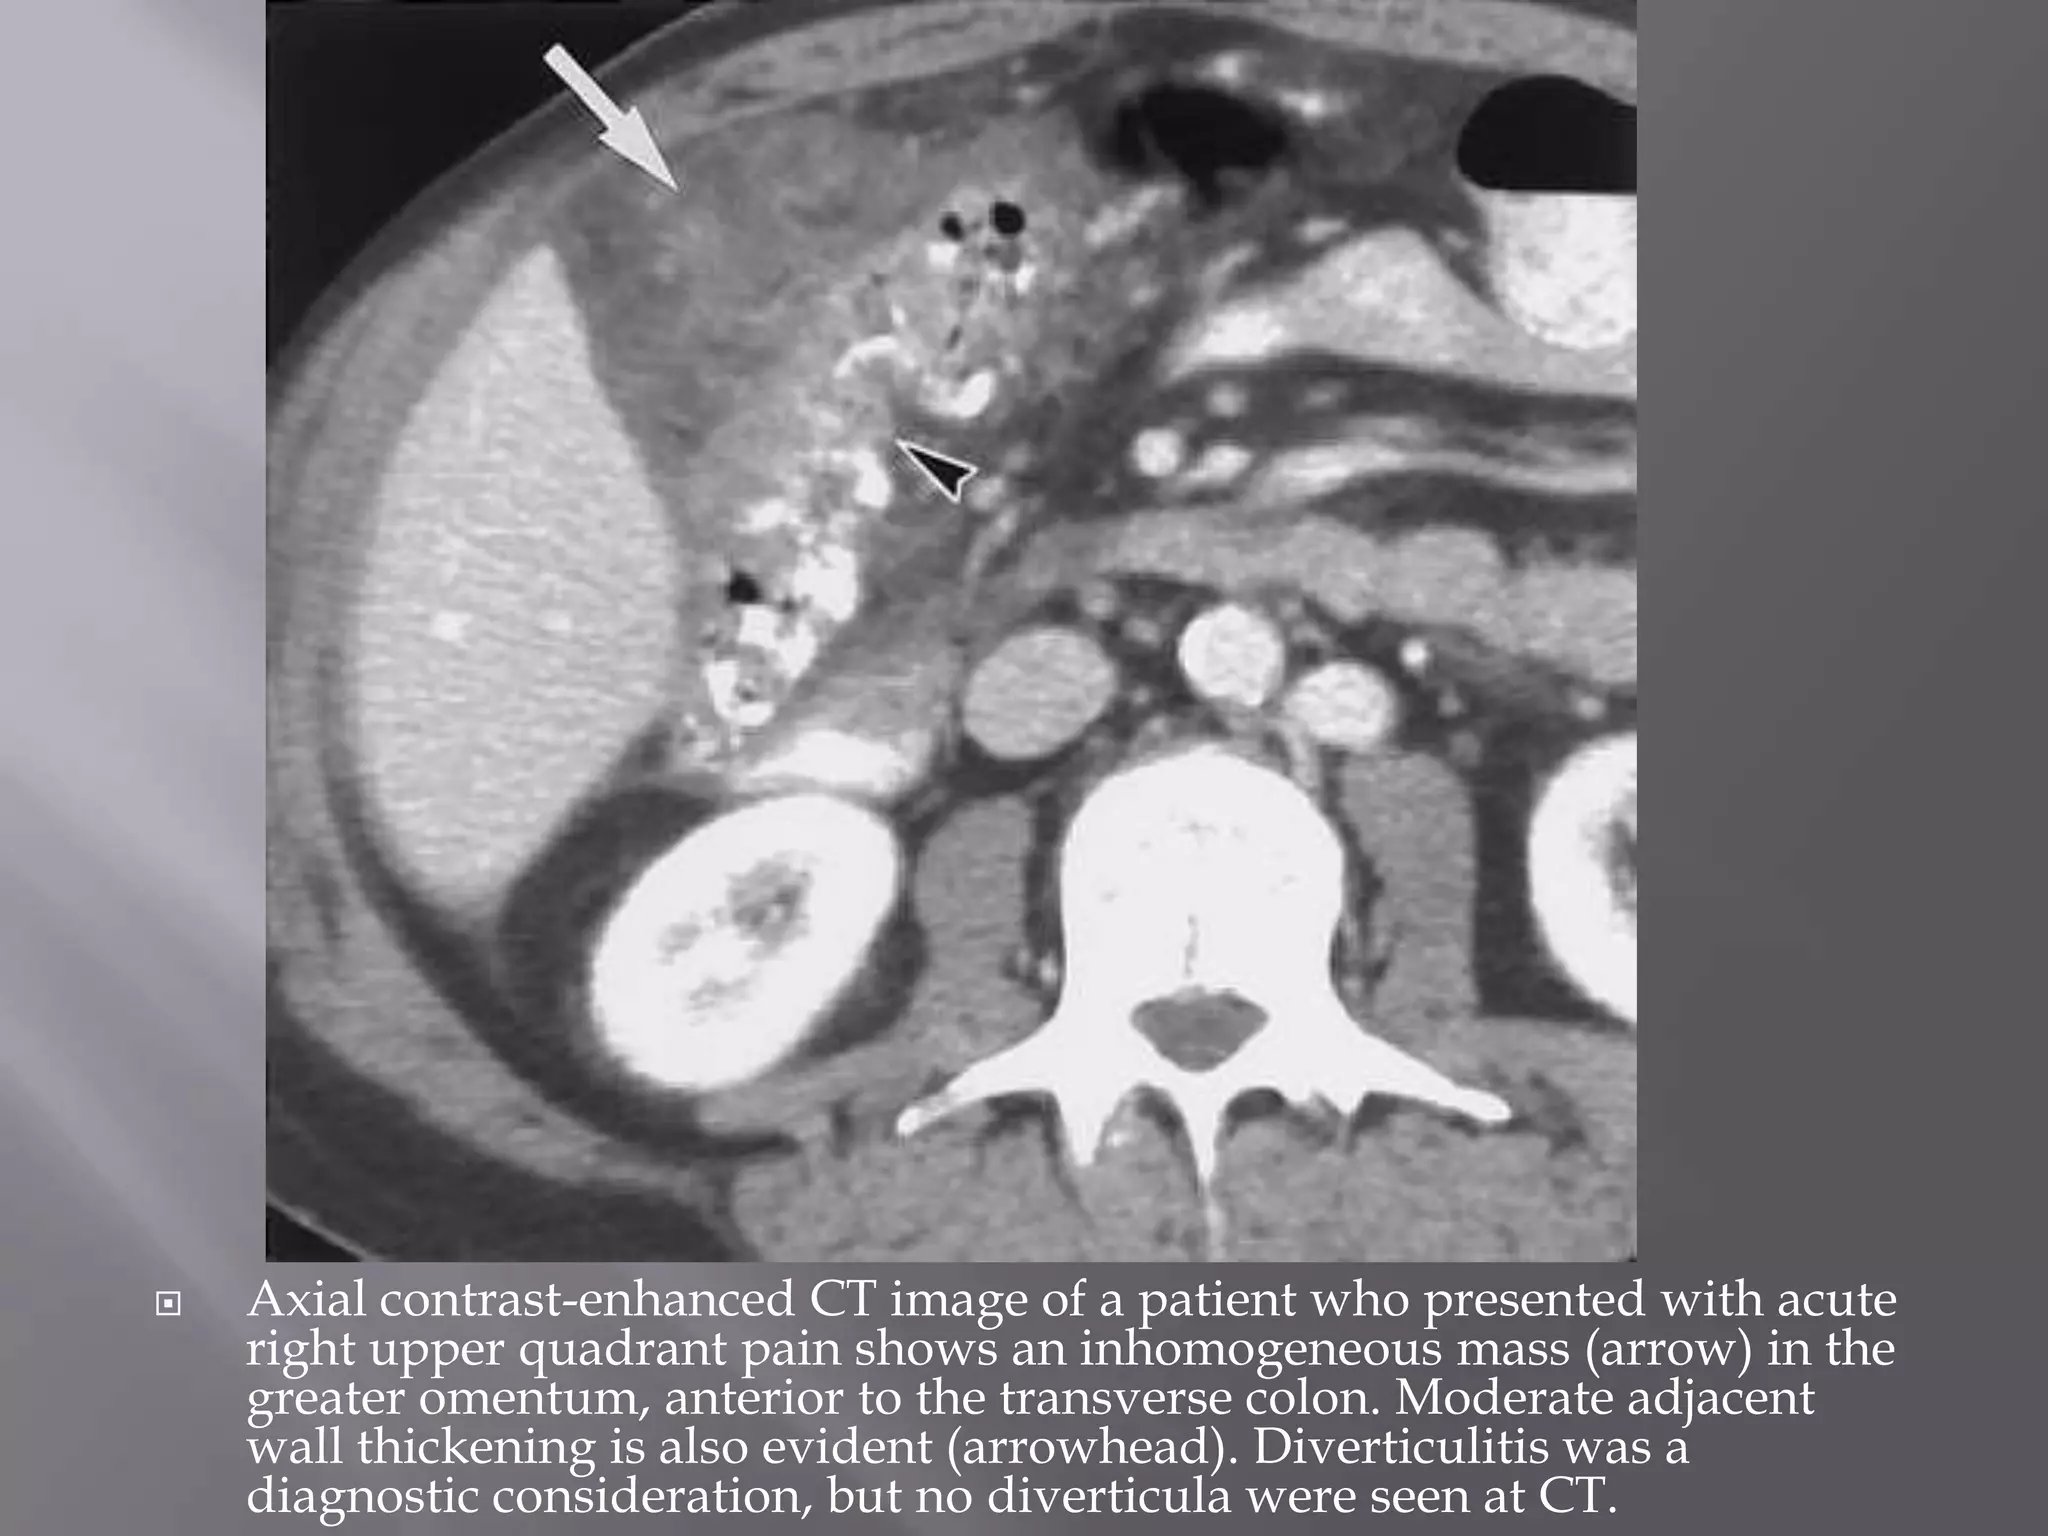

 Segmental omental infarction typically occurs

on the right, a predilection that has been

attributed to an embryologic variant of the

blood supply.

 Risk factors include obesity and recent surgery.

 On CT scans, the infarcted omentum appears

as a large, cakelike, high-attenuation fatty mass

centered in the omentum.

 Reactive bowel wall thickening may occur, but

the inflammatory process in the omentum

usually is disproportionately more severe.

 Axial contrast-enhanced CT image of a patient who presented with acute

right upper quadrant pain shows an inhomogeneous mass (arrow) in the

greater omentum, anterior to the transverse colon. Moderate adjacent

wall thickening is also evident (arrowhead). Diverticulitis was a

diagnostic consideration, but no diverticula were seen at CT.

 Segmental omentalinfarction typically occurs on the right, a predilection that has been attributed to an embryologic variant of the blood supply.  Risk factors include obesity and recent surgery.

 On CTscans, the infarcted omentum appears as a large, cakelike, high-attenuation fatty mass centered in the omentum.  Reactive bowel wall thickening may occur, but the inflammatory process in the omentum usually is disproportionately more severe.  Omental infarction and epiploic appendagitis may have similar appearances on CT scans.

 Axial contrast-enhancedCT image of a patient who presented with acute right upper quadrant pain shows an inhomogeneous mass (arrow) in the greater omentum, anterior to the transverse colon. Moderate adjacent wall thickening is also evident (arrowhead). Diverticulitis was a diagnostic consideration, but no diverticula were seen at CT.